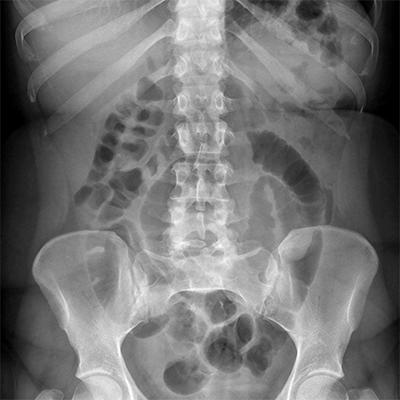

Présentation

La radiologie utilise les rayons X pour obtenir des images des structures internes du corps humain qui correspondent à une superposition. Les images obtenues sont appelées radiographies.

Nous réalisons tous les types de radiographie. La plupart ne nécessite aucune préparation spécifique.

Une échographie peut parfois être réalisée dans les suites pour approfondir le bilan et affiner le diagnostic.

Des précautions doivent être prises pour les femmes enceintes c’est pourquoi nous vous demandons de signaler votre grossesse préalablement.